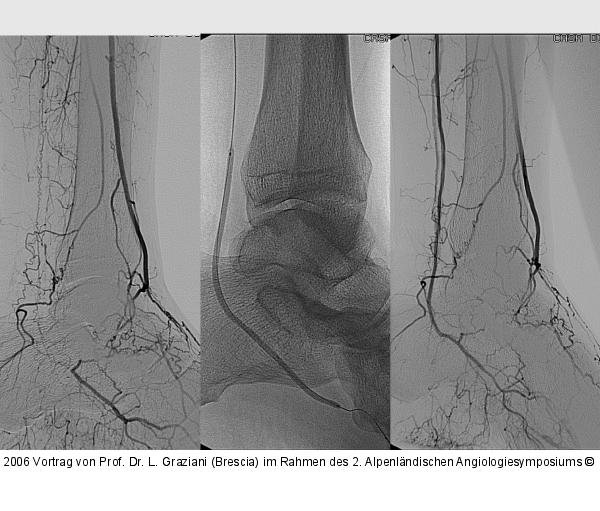

Vortrag von Prof. Dr. L. Graziani (Brescia) im Rahmen des 2. Alpenländischen Angiologiesymposiums

PTA of the foot arteries in diabetics: Extremities Extreme Angioplasty

Abbildung 36: PTA